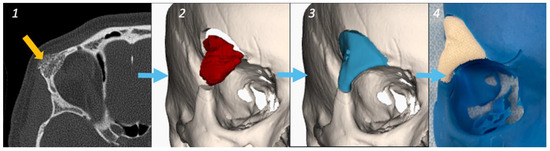

2.3. Intraosseous Hemangioma—Case 1

| Female | 42 | Intraosseous Hemangioma | Right supra-orbital rim | Hemicoronal | Supra-orbital and lateral orbital rim | None | Very good | 6 |